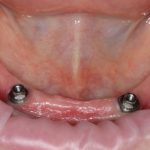

Рекомендации по установке имплантов. Для всех. Часть V.